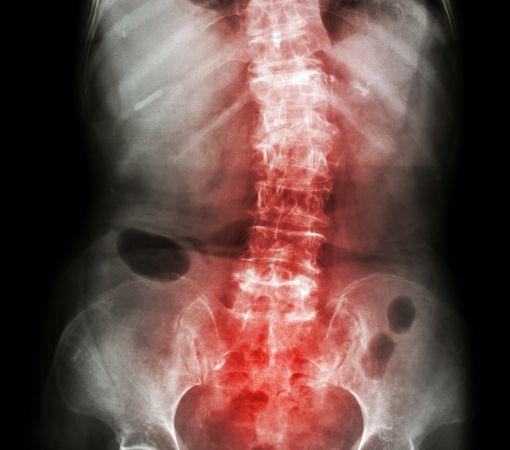

Spondylitis, often referred to as ankylosing spondylitis, is an inflammatory condition that primarily affects the spine, but it can also impact other joints and organs. This condition leads to the fusion of vertebrae, resulting in reduced flexibility and a hunched-forward posture. If left untreated, spondylitis can cause severe pain and permanent damage to the spine.

Accurate Diagnosis: We utilize advanced imaging techniques to precisely diagnose the extent of spondylitis, ensuring that your treatment plan is tailored to your specific condition.